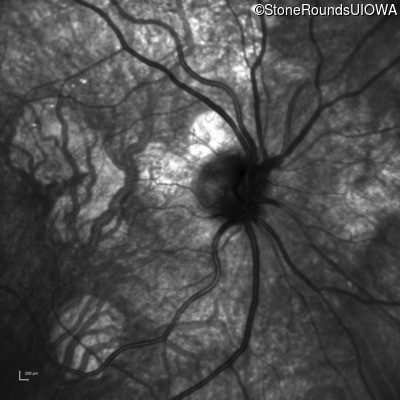

Age at visit: 31 years

This 31 year old woman had subtle macular abnormalities discovered incidentally earlier that year. Her medical history at the time was unremarkable except for gestational diabetes during her most recent pregnancy. Five years later she was diagnosed with type 2 diabetes managed with oral medication. Two years later she developed sufficient hearing loss that hearing aids were required. Her acuity remained 20/20 OU at that time.